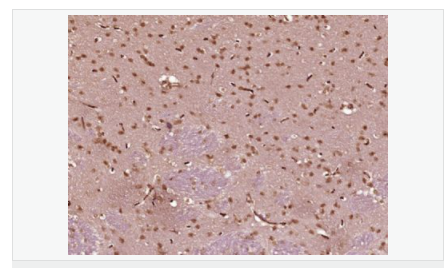

| 產(chǎn)品應用 | ELISA=1:5000-10000 IHC-P=1:100-500 IHC-F=1:100-500 ICC=1:100-500 IF=1:100-500 (石蠟切片需做抗原修復) not yet tested in other applications. optimal dilutions/concentrations should be determined by the end user. |

| 產(chǎn)品介紹 | This gene encodes a protein which contains a hinge region domain found in members of the SMC (structural maintenance of chromosomes) protein family. [provided by RefSeq, Dec 2011] Function: Required for maintenance of X inactivation in females and hypermethylation of CpG islands associated with inactive X. Involved in a pathway that mediates the methylation of a subset of CpG islands slowly and requires the de novo methyltransferase DNMT3B (By similarity). Required for DUX4 silencing in somatic cells. Subcellular Location: Chromosome DISEASE: The disease is caused by mutations affecting the gene represented in this entry. SMCHD1 mutations lead to DUX4 expression in somatic tissues, including muscle cells, when an haplotype on chromosome 4 is permissive for DUX4 expression. Ectopic expression of DUX4 in skeletal muscle activates the expression of stem cell and germline genes, and, when overexpressed in somatic cells, DUX4 can ultimately lead to cell death. Disease description:A degenerative muscle disease characterized by slowly progressive weakness of the muscles of the face, upper-arm, and shoulder girdle. The onset of symptoms usually occurs in the first or second decade of life. Affected individuals usually present with impairment of upper extremity elevation. This tends to be followed by facial weakness, primarily involving the orbicularis oris and orbicularis oculi muscles. SWISS: A6NHR9 Gene ID: 23347 Database links: Entrez Gene: 23347 Human Entrez Gene: 74355 Mouse Omim: 614982 Human SwissProt: A6NHR9 Human SwissProt: Q6P5D8 Mouse Unigene: 8118 Human Unigene: 194450 Mouse Important Note: This product as supplied is intended for research use only, not for use in human, therapeutic or diagnostic applications. |